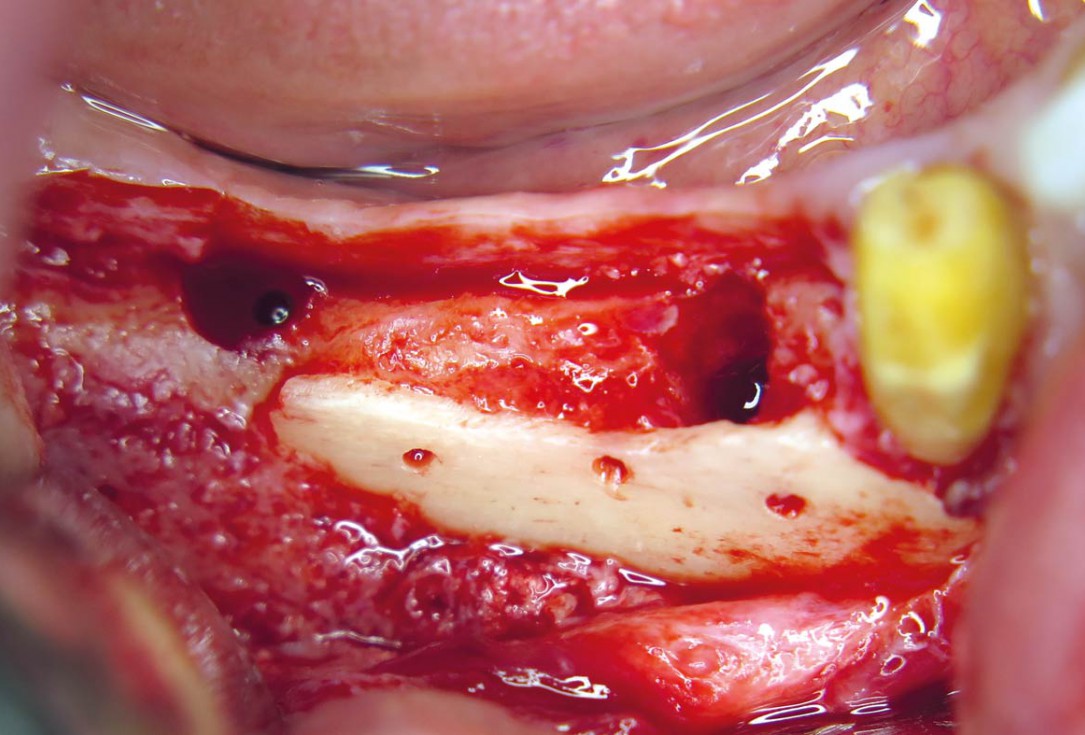

03 / 20 - Flap projection shows pronounced bone lossHorizontal ridge augmentation with maxgraft® cortico - M.Sc. E. Kapogianni